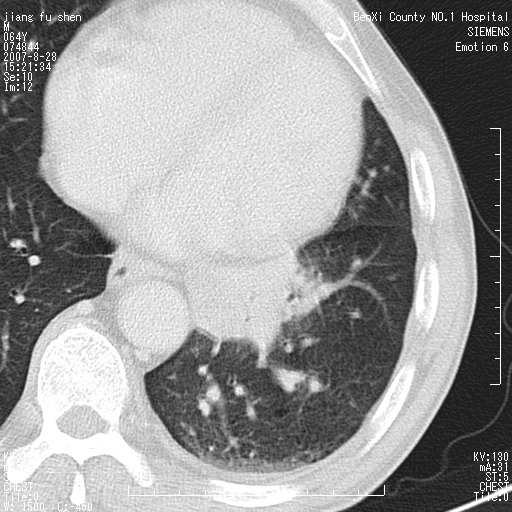

男、64、咳嗽、发烧一周、左肺呼吸音稍弱。既往肺结核,右手结核。

本次扫描患者未带原片,左肺下叶发现病灶。左肺上叶空洞,5组淋巴结肿大,1cm左右。

追问病史三月份ct扫描左肺上叶空洞,医大诊断肺结核。

平扫20-33hu

增强31-33hu

1分半44-52

2分55-67

左肺下叶前内基底段支气管明显偏心性狭窄,周围分叶状肿块,伴有阻塞性肺炎,支持肺癌可能性大。

考虑左肺中央型肺癌并阻塞性肺炎

病灶边缘可见多量较长棘影及纤维条索状影,除外病灶边缘较光整,病灶有分叶表现,但多表现为较浅分叶,且向周围伸出之叶多呈尖角改变,且边缘较光整,病灶增强呈中度延时增强,且早期及中期仅轻度增强,结合患者病史,多考虑继发型肺结核,炎性增殖灶形成,不除外肺癌

左下叶支气管变窄,管腔光滑。软组织形状不规侧,分叶呈角形。结合病史考虑结核可能性大。肺癌不除。